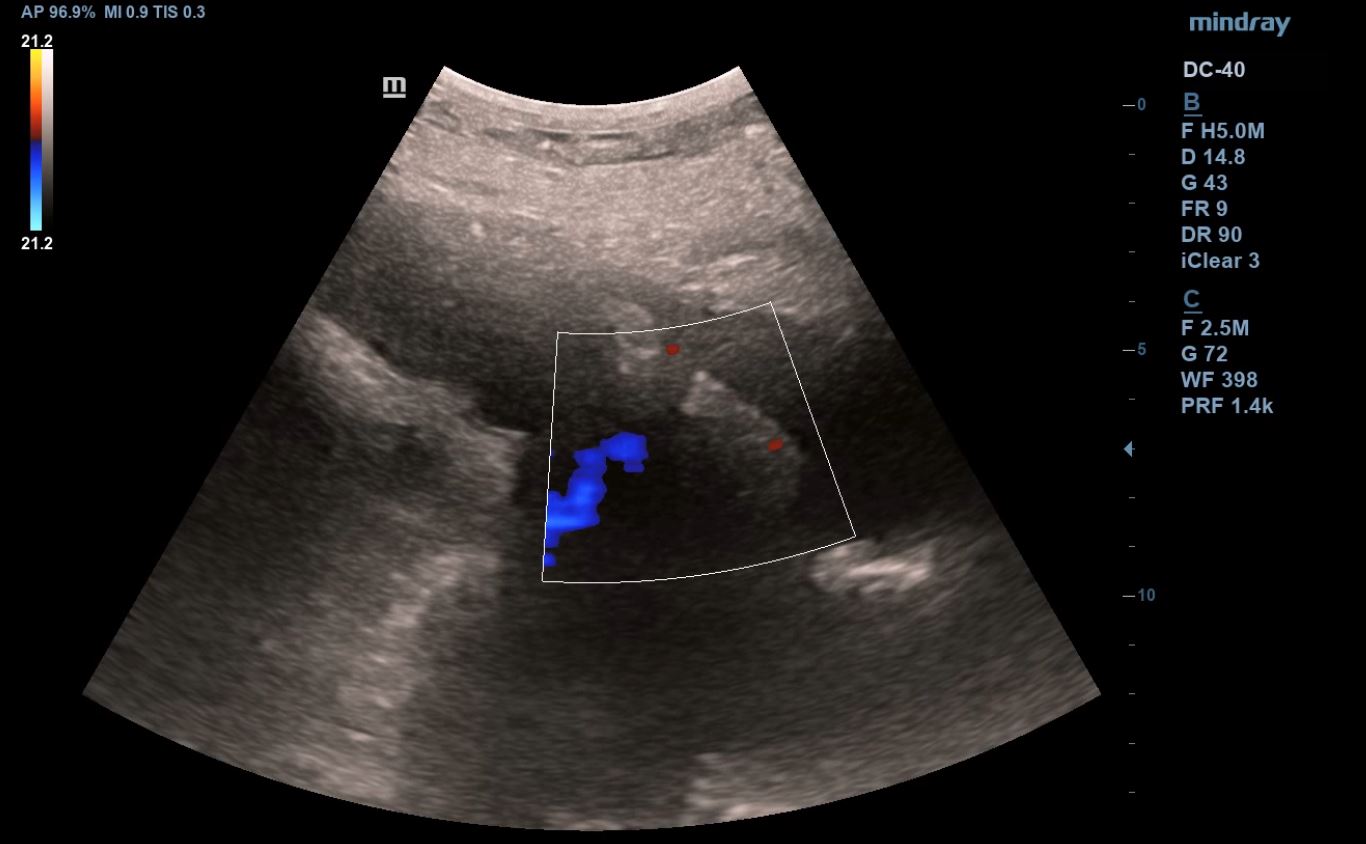

Se realiza ecografía clínica abdominal y pulmonar en la consulta, donde se visualiza líquido libre en espacio hepatorenal, esplenorenal y espacio de Douglas. En región pélvica presenta masa de aspecto heterogéneo con zonas anecoicas de 12 x 10 cm, con mapa color positivo. En la ecografía pulmonar presenta derrame pleural derecho.